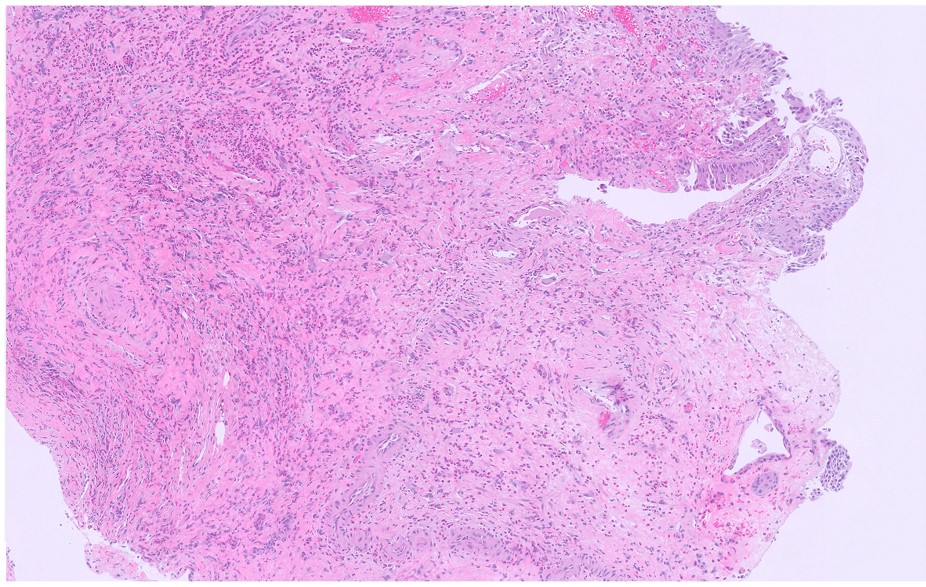

Microscopic image possibly detecting cancerous areas in human tissue

What is the most likely diagnosis?

1. Radiation cystitis

2. Cystitis cystica

3. Invasive urothelial carcinoma

4. carcinoma in situ

Radiation cystitis